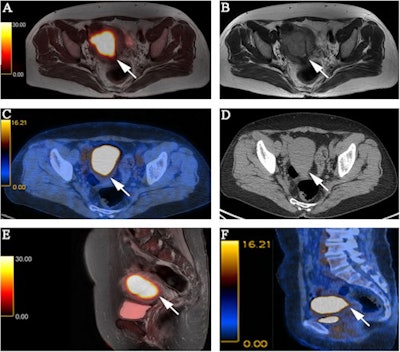

FIGO stage II pathologically confirmed moderately differentiated adenocarcinoma in a 57-year-old female patient. (A) Axial PET/MR images. (B) Axial MR T2-weighted images. (C) Axial PET/CT images. (D) Axial CT images. (E) Sagittal PET/MR images. (F) Sagittal PET/CT images. PET/MRI and MRI show the endometrial carcinoma invading the cervical stroma. PET/CT also shows the endometrial carcinoma invading the cervical stroma, yet the extension of the tumor is difficult to determine. The PET/MRI and PET/CT staging were consistent with the pathological stage, namely FIGO stage II. The white arrow indicates endometrial carcinoma. Image courtesy of BMC Cancer.

FIGO stage II pathologically confirmed moderately differentiated adenocarcinoma in a 57-year-old female patient. (A) Axial PET/MR images. (B) Axial MR T2-weighted images. (C) Axial PET/CT images. (D) Axial CT images. (E) Sagittal PET/MR images. (F) Sagittal PET/CT images. PET/MRI and MRI show the endometrial carcinoma invading the cervical stroma. PET/CT also shows the endometrial carcinoma invading the cervical stroma, yet the extension of the tumor is difficult to determine. The PET/MRI and PET/CT staging were consistent with the pathological stage, namely FIGO stage II. The white arrow indicates endometrial carcinoma. Image courtesy of BMC Cancer.In addition, an analysis of quantitative measures based on F-18 FDG PET/MRI radiotracer uptake by the tumors and nearby tissue were significantly different between stage I and stage III tumors, the authors wrote.

"PET/MRI had higher accuracy for endometrial carcinoma staging, mainly for FIGO stage I tumors. This was mainly owing to PET/MRI having higher diagnostic accuracy for detecting the depth of myometrial invasion," they wrote.